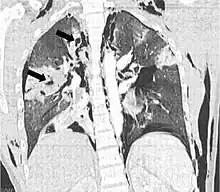

Coronal CT scan showing lucencies (pale areas in radiography) in the lung caused by pulmonary lacerations on the left of the image (black arrows)

Pulmonary laceration may not be visible using chest X-ray because an associated pulmonary contusion or hemorrhage may mask it.[1][9] As the lung contusion clears (usually within two to four days), lacerations begin to become visible on chest X-ray.[3] CT scanning is more sensitive and better at detecting pulmonary laceration than X-rays are,[1][5][12][15] and often reveals multiple lacerations in cases where chest X-ray showed only a contusion.[12] Before CT scanning was widely available, pulmonary laceration was considered unusual because it was not common to find with X-ray alone.[12] On a CT scan, pulmonary lacerations show up in a contused area of the lung,[9] typically appearing as cavities filled with air or fluid[16] that usually have a round or ovoid shape due to the lung's elasticity.[4]